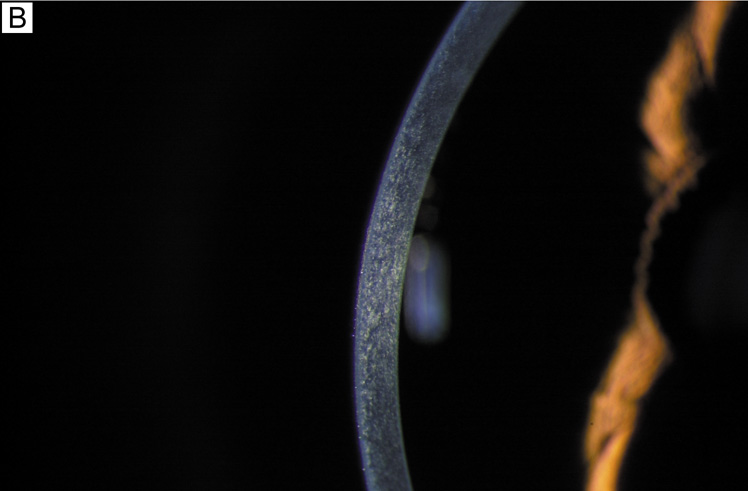

Fig. 1. (A) Diffuse illumination slit-lamp view of the human cornea. (B) Slit-beam illumination slit-lamp view of the human cornea shows an optical section of the tissue. Notice the slight light scattering that occurs in the tissue, mainly from cellular components in cornea. (C) Histologic diagram of the major cellular and extracellular matrix components of the human cornea (toluidine blue 25×).